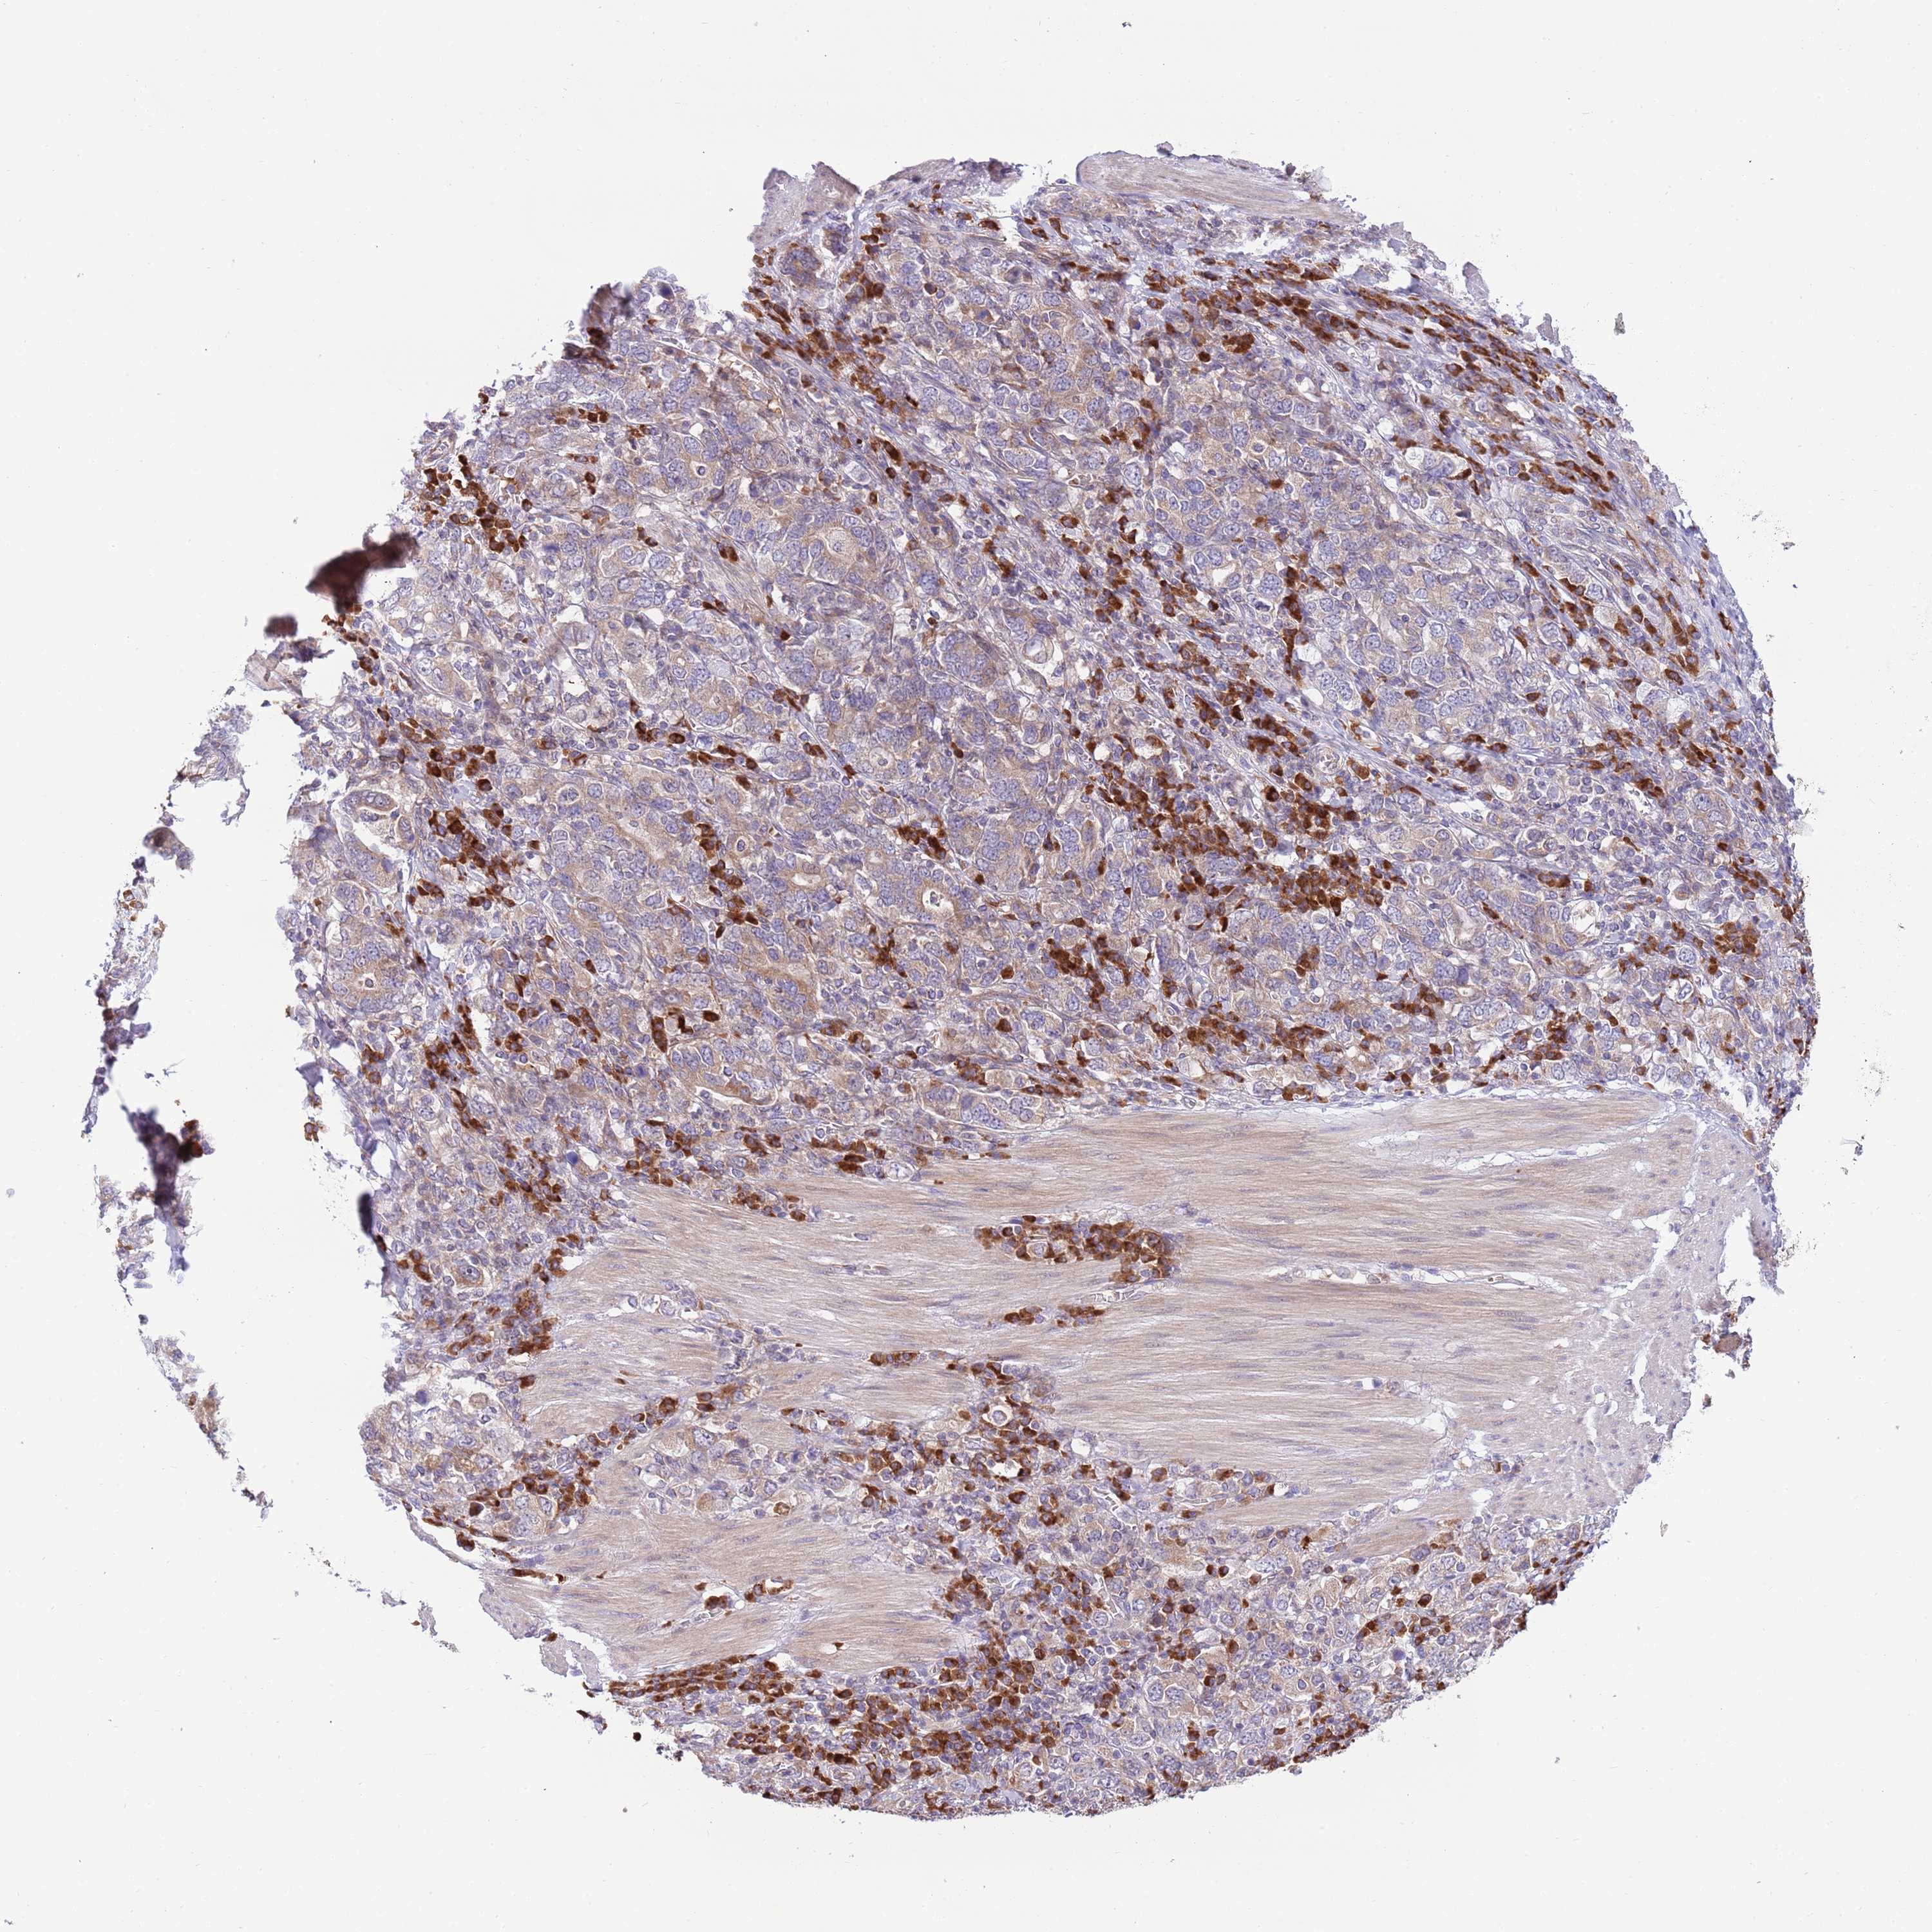

STOMACH CANCER - Protein expressioni

A mouse-over function shows sample information and annotation data. Click on an image to view it in a full screen mode. Samples can be filtered based on level of antibody staining by selecting one or several of the following categories: high, medium, low and not detected. The assay and annotation is described here.

Note that samples used for immunohistochemistry by the Human Protein Atlas do not correspond to samples in the TCGA dataset.

Antibody stainingi

Antibody staining in the annotated cell types in the current human tissue is reported as not detected, low, medium, or high, based on conventional immunohistochemistry profiling in selected tissues. This score is based on the combination of the staining intensity and fraction of stained cells.

Each image is clickable and will lead to virtual microscopy that enables deeper exploration of all samples and also displays staining intensity scores, fraction scores and subcellular localization as well as patient and tissue information for each sample.

Antibody HPA049472

Staining

High

Medium

Low

Not detected

Intensity

Strong

Moderate

Weak

Negative

Quantity

>75%

75%-25%

<25%

None

Location

Nuclear

Cytoplasmic/membranous

Cytoplasmic/membranous,nuclear

Adenocarcinoma, NOS